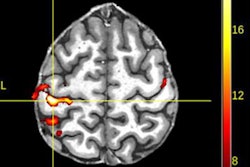

In a trial approved by the U.K.'s Health Research Authority, GE and NCIMI will develop and test imaging and vital signs algorithms that can detect COVID-19 pneumonia and predict which patients might develop severe respiratory distress, a risk factor for mortality and long-term lung function problems.

The algorithms will be designed using medical imaging, laboratory, and clinical data from thousands of patients in the NCIMI NHS partner hospitals database and National COVID-19 Chest Imaging Database. Then, researchers from Oxford will use the algorithms to study COVID-19 pneumonia and evaluate whether the software aids in patient management, including triage, acute monitoring, interventions, discharge, and follow-up.